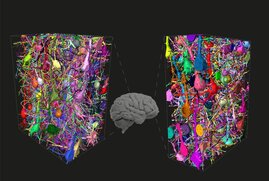

Die Analyse des menschlichen Gehirns ist ein zentrales Ziel der Neurowissenschaften. Aus methodischen Gründen hat sich die Forschung jedoch weitgehend…